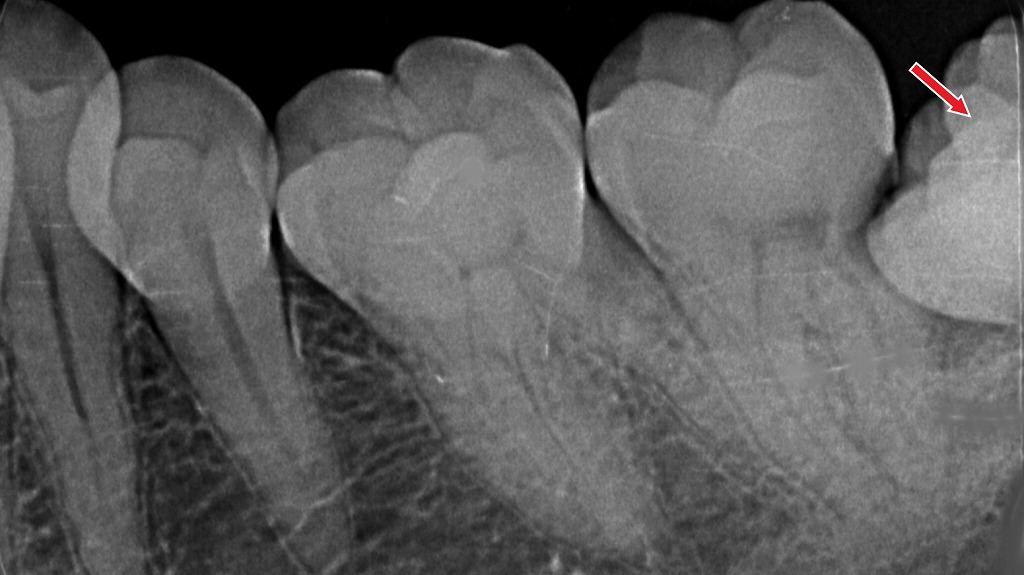

矯正治療中の歯垢染め出し液でチェック

この画像は、矯正治療中の歯にプラーク(歯垢)染め出し液を使用した状態を示しています。

🦷 全体の説明

歯の表面に紫〜ピンク色に染まっている部分がありますが、これはプラーク(歯垢)染色剤によって可視化された汚れです。矯正装置(ブラケットやワイヤー)がついていると、歯ブラシが届きにくくなり、ブラケットの周囲やワイヤーの下にプラークが残りやすくなります。

🔍 各部位のポイント

① ブラケット周辺のプラーク

- 金属のブラケットのまわり、特に**歯とブラケットの境目や歯頸部(歯ぐきに近い部分)**が濃く染まっています。

- これは歯ブラシの毛先が届きにくいため、プラークが残存している証拠です。

- 放置すると、ホワイトスポット(初期虫歯)や歯肉炎の原因になります。

② 歯肉の腫れと発赤

- 歯ぐきが赤く、やや腫れて見える部分があります。

- プラークの刺激で歯肉炎を起こしている可能性があり、出血しやすくなっています。

③ 染め出しの色の意味

- 濃い紫色:古いプラーク(数日以上残っているもの)

- 明るいピンク色:新しいプラーク(直近で付着したもの)

→ ブラッシングが不十分な部位を視覚的に確認するために使用します。

🪥 清掃方法のポイント

💡 通常の歯ブラシ

- ブラケットの上・下・正面を分けて磨く意識が大切です。

- ワイヤー下の清掃も角度を変えて行います。

💡 ワンタフトブラシの使用

- 写真のようにブラケット周囲に汚れが残りやすい場合、

ワンタフトブラシ(毛束が1本の小さいブラシ)が非常に効果的です。 - ブラケットの上下や歯と歯の間、ワイヤー下を小刻みに動かして磨くと、プラークを除去しやすくなります。

⚠️ 放置すると…

- プラーク内の細菌が酸を出し、**脱灰(初期虫歯)**が進行。

- 白く濁る「ホワイトスポット」や、装置除去後の虫歯・歯肉退縮につながります。